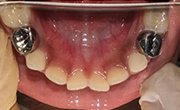

Our state-of-the-art manufacturing process for preformed dental crowns ensures highly accurate, custom-fit restorations, enhancing both clinical outcomes and patient satisfaction.

With faster production times, enhanced durability, and a more comfortable fit, Rainbow Crown elevates the standard of care for both practitioners and patients, setting a new benchmark for modern dental restorations.

Our crowns are crafted with unmatched accuracy using the latest digital technology, ensuring a perfect fit and superior functionality for every patient.

We use only the finest materials ensuring that every crown offers exceptional strength, wear resistance, and a natural appearance.